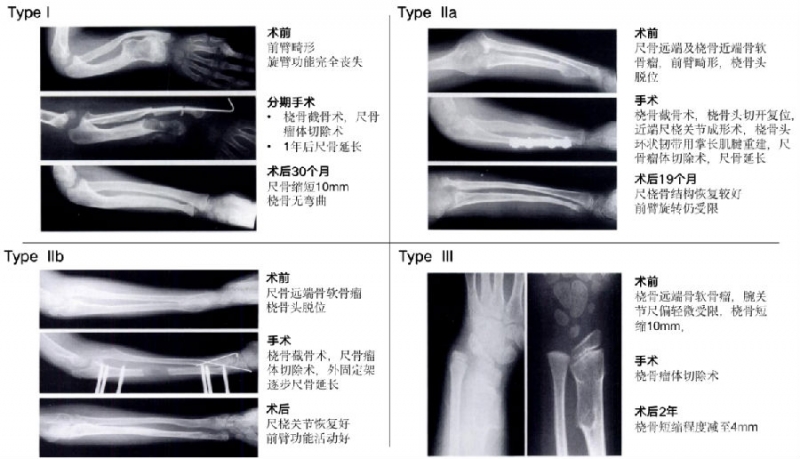

因此,构建针对性的临床分型是帮助手术方式选择及提高术后疗效的有效手段。1989年,日本大阪大学医学院Masada等研究报道了一种适用于MHE致前臂畸形的临床分型(I、IIa、IIb、III型),被广泛接受并沿用至今(图2)。

图2. MHE前臂畸形-Masada分型

Masada等对13例患有MHE伴前臂畸形的患者按术前影像结果及临床症状进行分型,并进行了对应的手术治疗及术后随访复查。随访结果显示这些患者术后均获得了较为理想的疗效(图5)。

图5. 各类Masada分型手术治疗病例